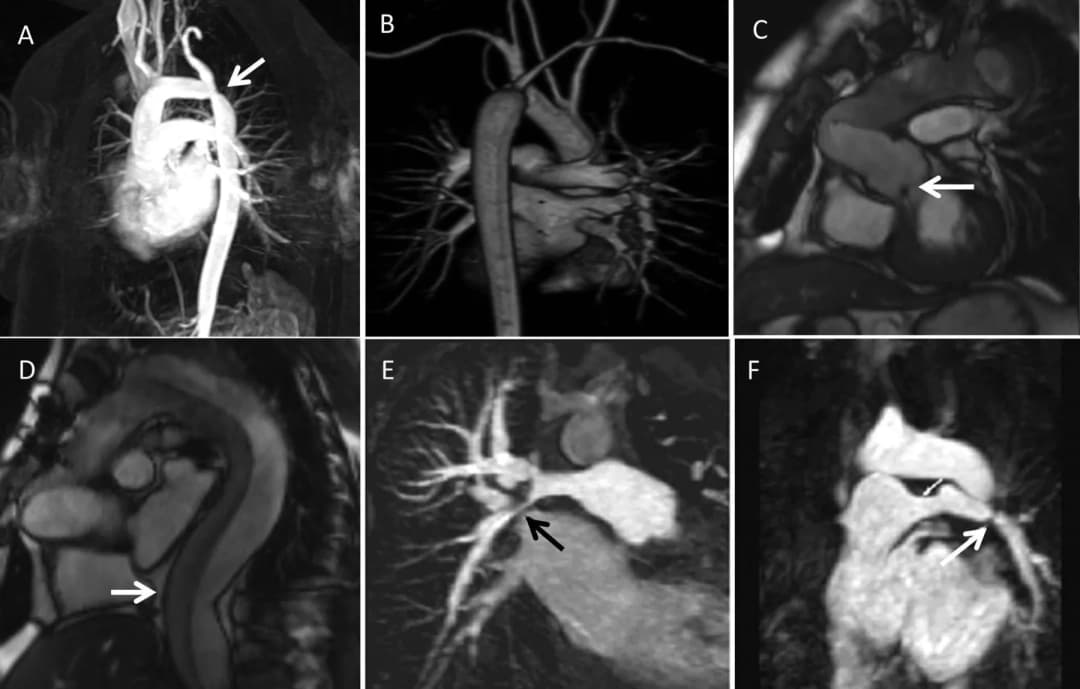

### Những tiến bộ trong kỹ thuật hình ảnh và chẩn đoán suy thất phải

Trong những năm gần đây, công nghệ hình ảnh y khoa...

suy timsiêu âm timbệnh timChẩn đoán suy timchụp cộng hưởng từ tim

Ứng dụng của cộng hưởng từ tim mạch trong chẩn đoán suy tim

# Suy Tim và Vai Trò của Chụp Cộng Hưởng Từ Tim